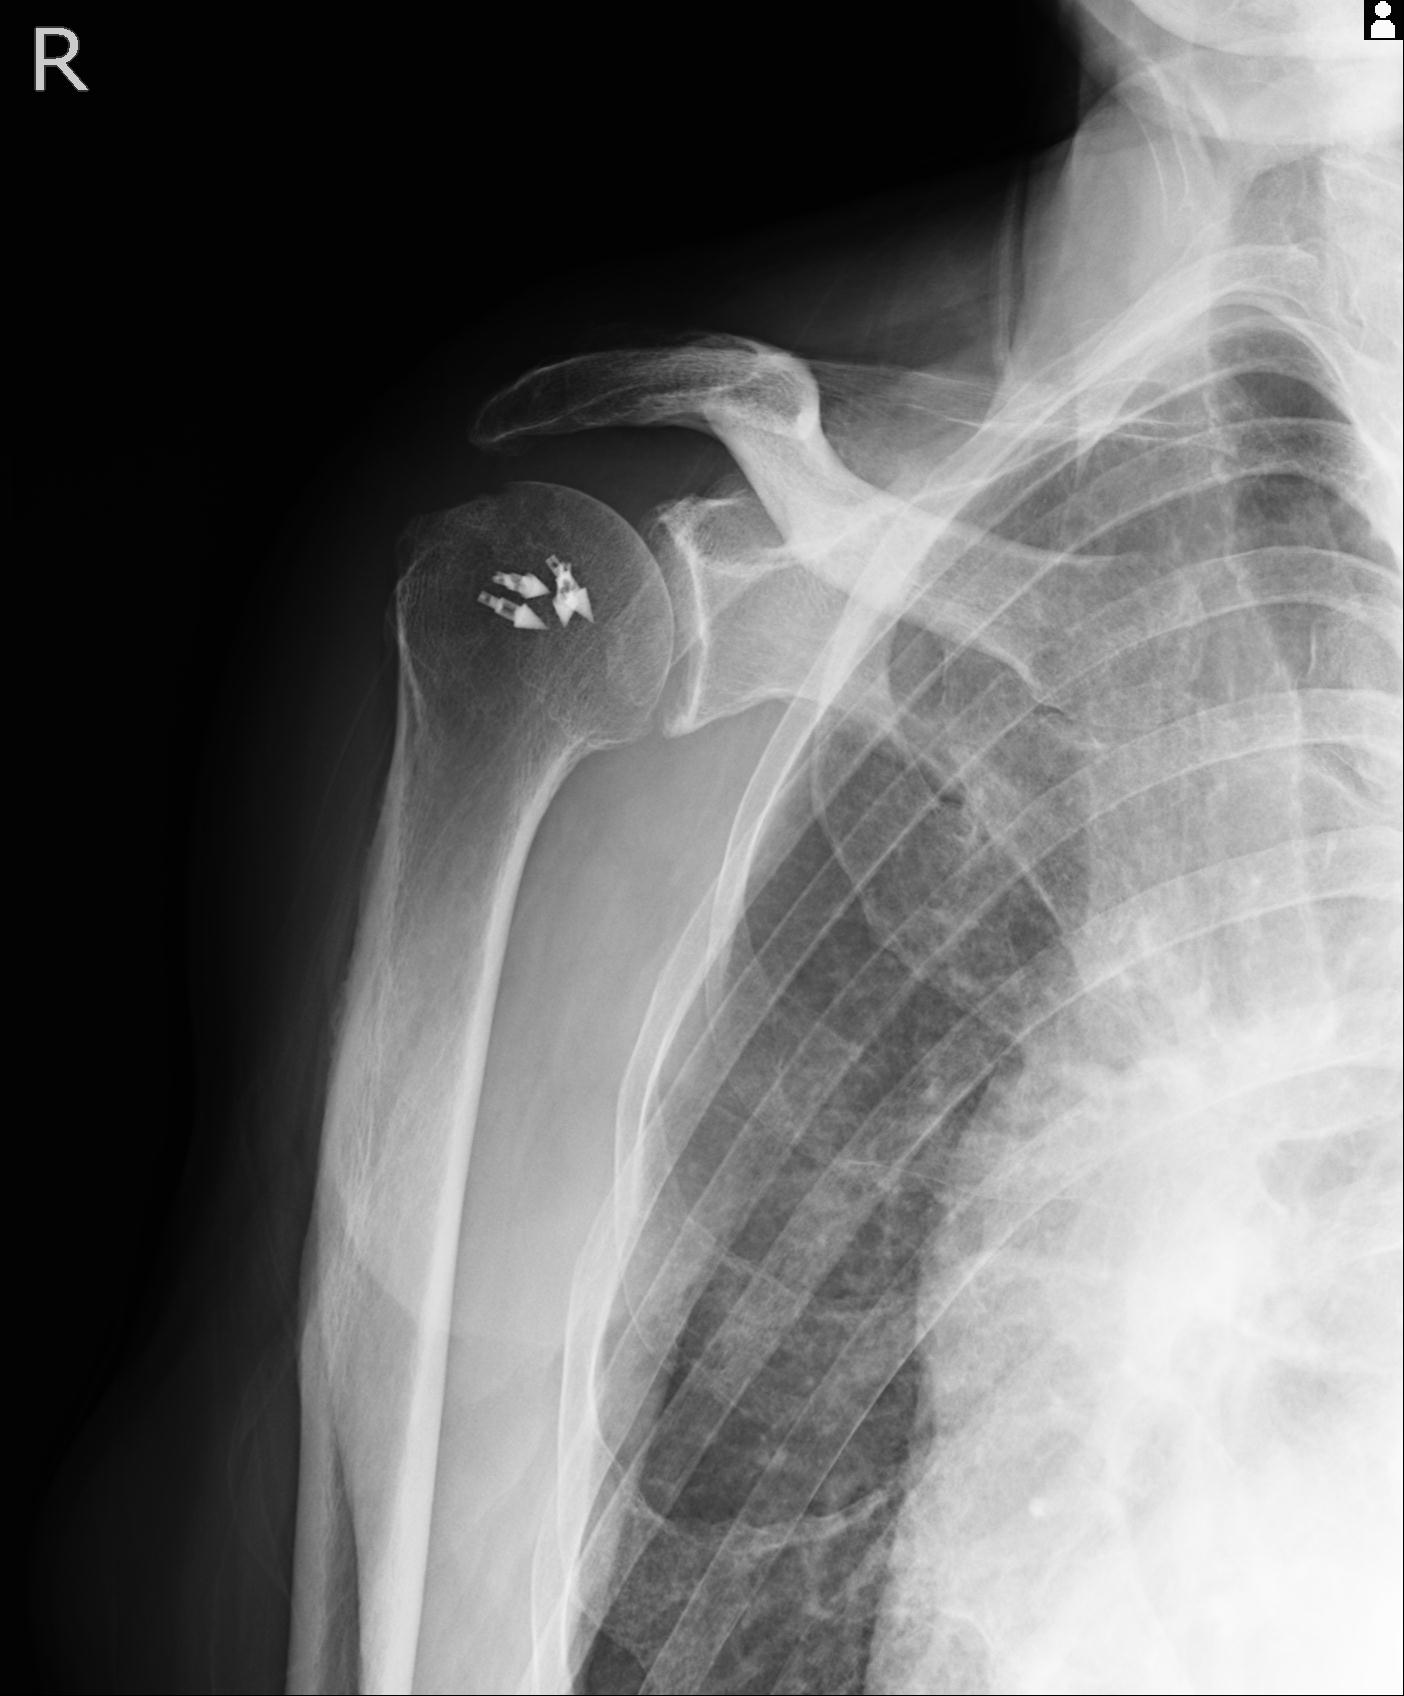

60058 3/9 11/4 右肩 2R+MRI 73歳男性 肩腱板損傷